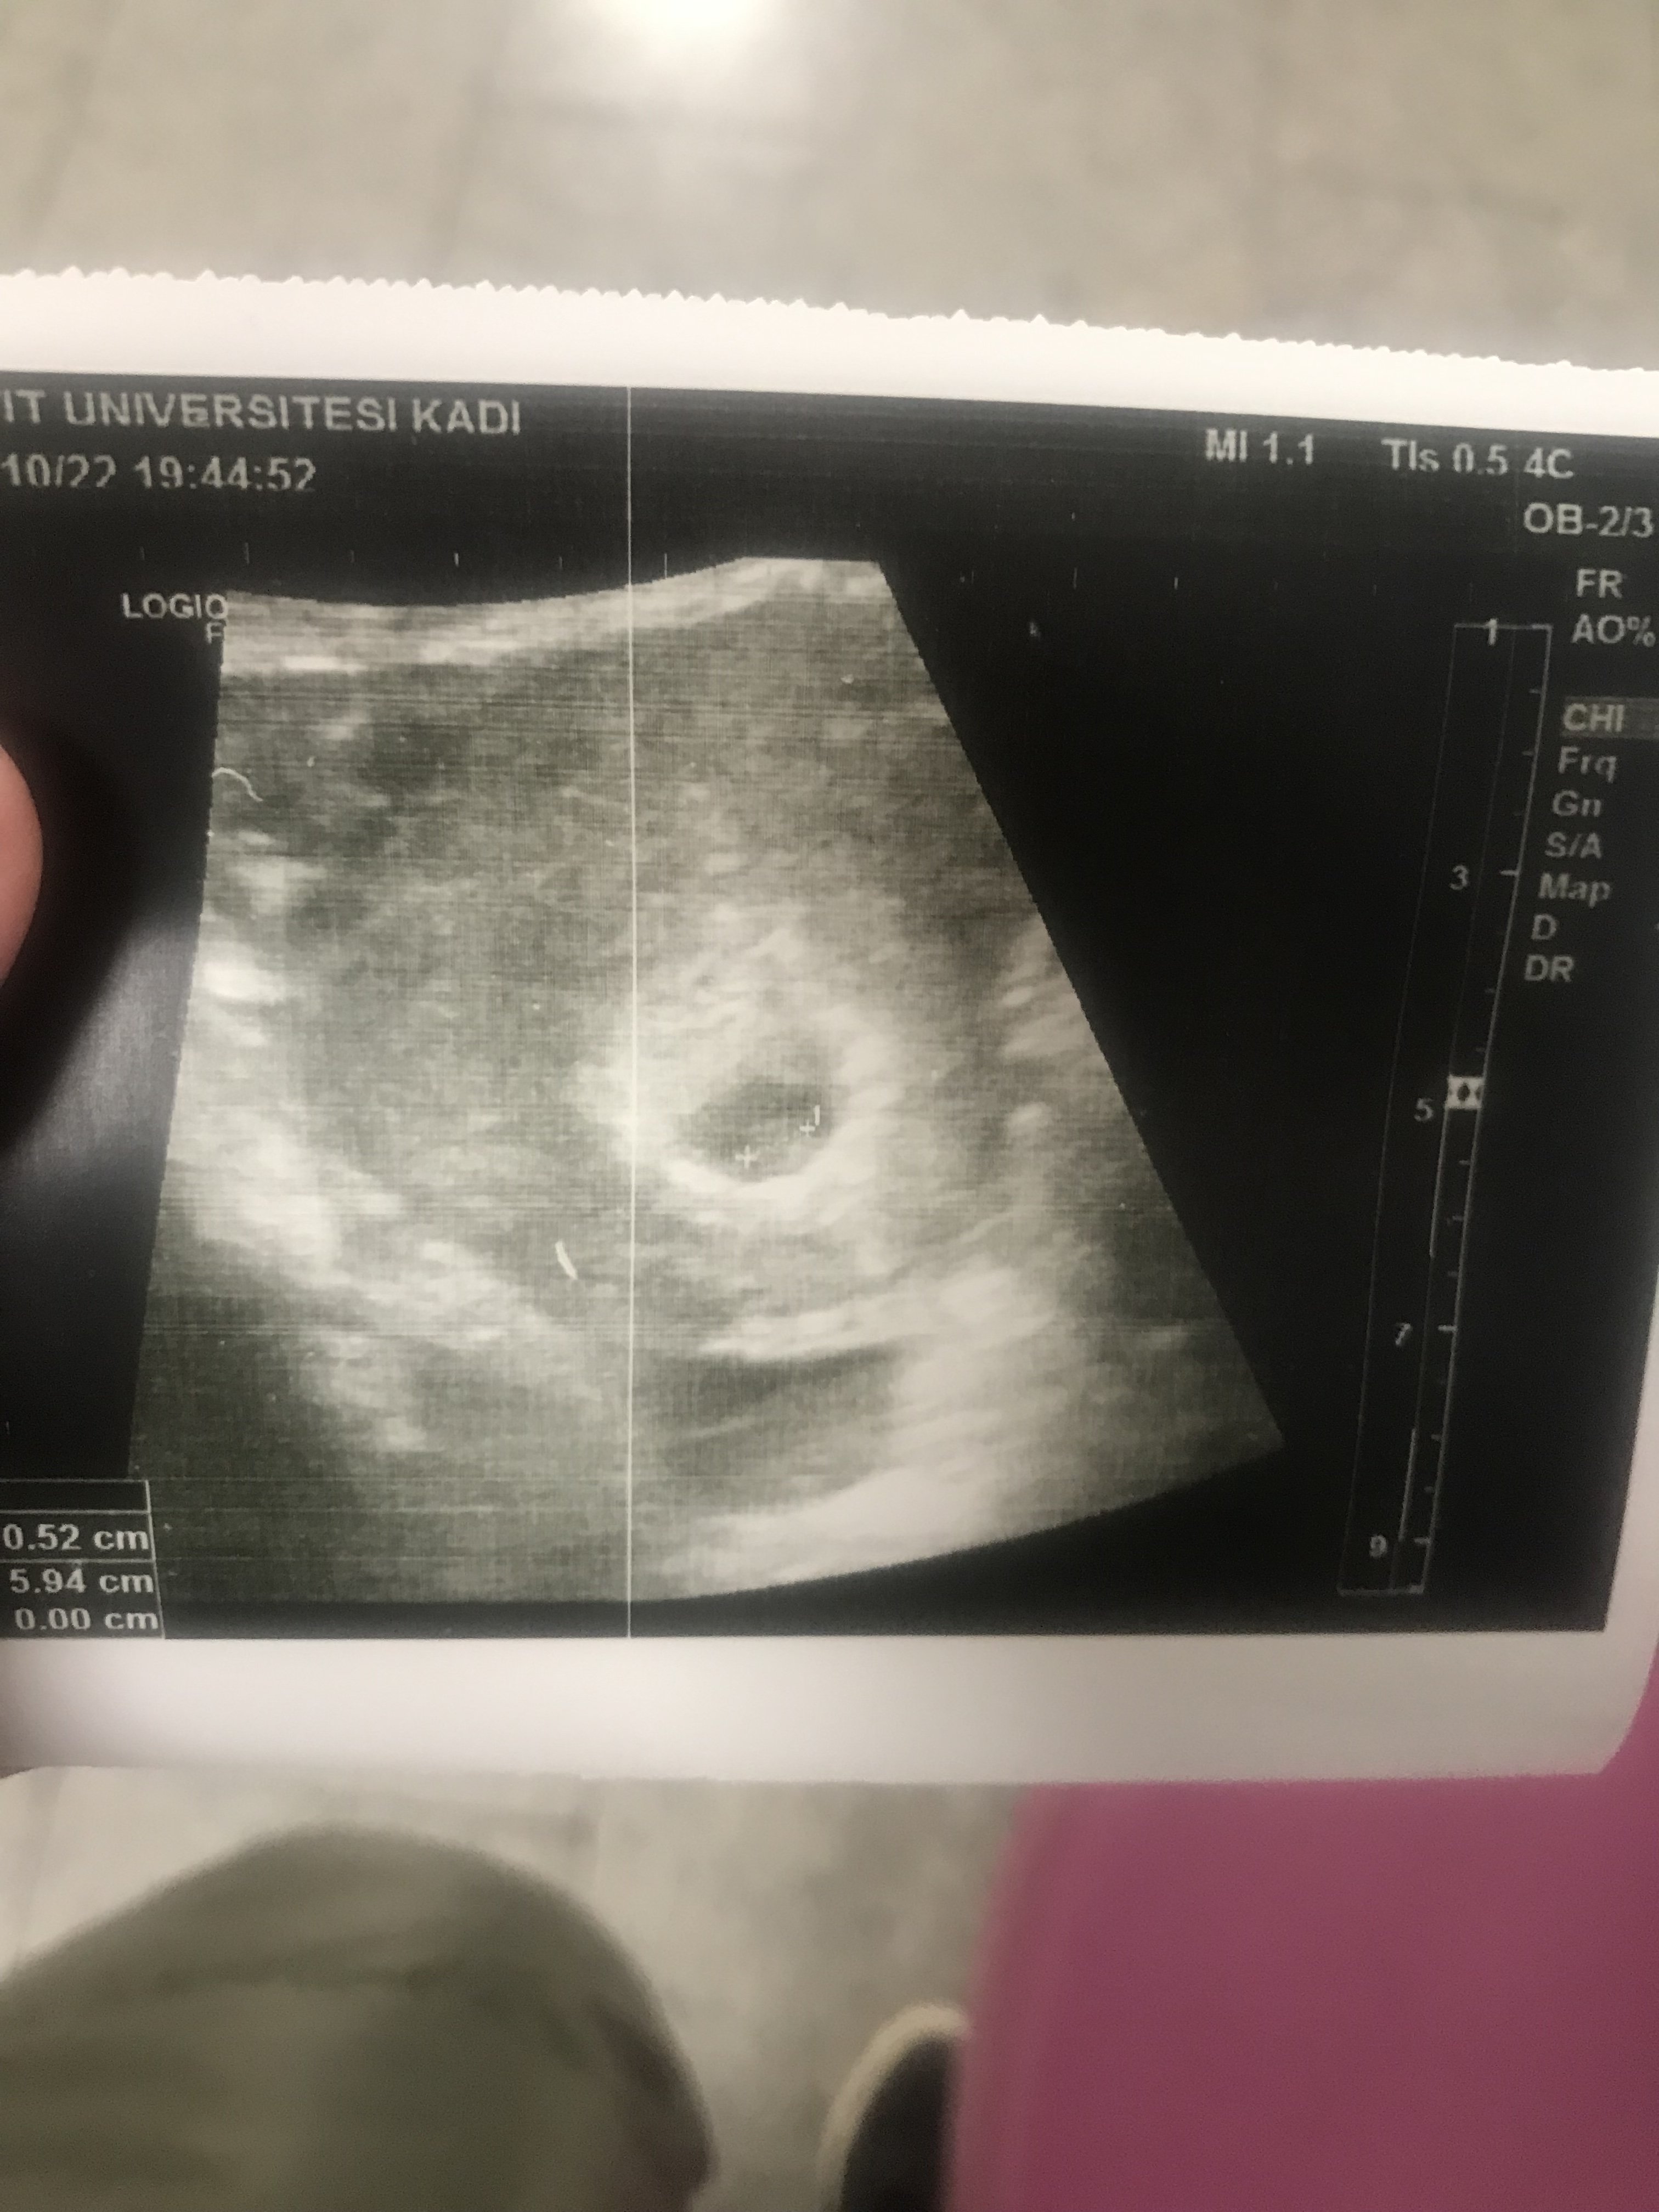

• IMG-20221019-WA0023.jpg

IMG-20221019-WA0023.jpg

99,6 KB · Görüntüleme: 137

Bi tanem tekrar selamlar yok hayatım çok küçük vallahi göremiyorum hakkını helal et lütfen. Resimler olmuş sıkıntı yok ama sıkıntı görünmeyecek kadar yeni ve küçük olması netlik yok hayatım kusura bakma lütfen.